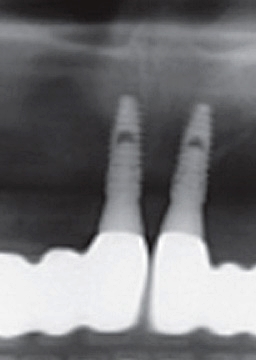

하지만 풀아치임플란트 시술은 기존 임플란트 치료와는 그 차이가 확연하게 나다 보니, 무치악 환자분들께서 선호하는 임플란트 시술이라고 하였어요. 이는 상악 하악에 각각 4개에서 6개까지만 임플란트를 식립하다 보니, 경제적인 측면에서 훨씬 부담이 덜할 수 있는 임플란트 시술이라고 하였어요. 이렇게 임플란트 시술을 한 후에 하나의 보철물을 이에 연결하다 보니 전체 치아의 저작기능이 회복할 수 있다고 하였어요.

풀아치임플란트 시술이란 상악 하악에 각각 4개에서 6개까지 인공 치근을 심어 잇몸뼈에 심은 후에 하나로 연결된 보철물을 임플란트에 고정하는 시술을 말하였어요. 이러한 풀아치 임플란트 치료는 발치부터 임플란트 시술, 보철물 장착까지 전 과정을 3D CT와 같은 디지털 시스템에 기반하다 보니 무절개 수술이 가능할 수 있었어요. 이러한 풀아치임플란트 시술은 기존 임플란트에 비하여 식립 개수가 절반 정도이다 보니 경제적인 부담이 줄어들 수 있었어요.

또한 뼈 이식 없이 남아 있는 건강한 잇몸 뼈를 이용하여 수술이 가능해지며, 이로 인하여 잃어버렸던 저작기능을 회복할 수 있기에 기능적인 측면에서도 큰 기대효과를 볼 수 있었어요. 게다가 인공치근 개수가 적다 보니 잇몸 절개로 인해 발생된 출혈을 줄일 수 있었으며, 수술 시간 및 회복 기간이 짧다 보니 전체적인 치료 기간이 일반 임플란트 치료에 비하여 짧을 수 있었어요.